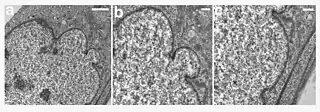

| A young girl with progeria (left). A healthy cell nucleus (right, top) and a progeric cell nucleus (right, bottom). | |

HGPS is caused by mutations that weaken the structure of the cell nucleus, making normal cell division difficult. The histone mark H4K20me3 is involved and caused by de novo mutations that occur in a gene that encodes lamin A. Lamin A is made but is not processed properly. This poor processing creates an abnormal nuclear morphology and disorganized heterochromatin. Patients also do not have appropriate DNA repair, and they also have increased genomic instability.[14]

Before the late 20th century, research on progeria yielded very little information about the syndrome. In 2003, the cause of progeria was discovered to be a point mutation in position 1824 of the LMNA gene, which replaces a cytosine with thymine.[19] This mutation creates a 5' cryptic splice site within exon 11, resulting in a shorter than normal mRNA transcript. When this shorter mRNA is translated into protein, it produces an abnormal variant of the prelamin A protein, referred to as progerin. Progerin's farnesyl group cannot be removed because the ZMPSTE24 cleavage site is lacking from progerin, so the abnormal protein is permanently attached to the nuclear rim. One result is that the nuclear lamina does not provide the nuclear envelope with enough structural support, causing it to take on an abnormal shape.[20] Since the support that the nuclear lamina normally provides is necessary for the organizing of chromatin during mitosis, weakening of the nuclear lamina limits the ability of the cell to divide.[21] However, defective cell division is unlikely to be the main defect leading to progeria, particularly because children develop normally without any signs of disease until about one year of age. Farnesylated prelamin A variants also lead to defective DNA repair, which may play a role in the development of progeria.[22] Progerin expression also leads to defects in the establishment of fibroblast cell polarity, which is also seen in physiological aging.[23]

In HGPS, the recognition site that the enzyme requires for cleavage of prelamin A to lamin A is mutated. Lamin A cannot be produced, and prelamin A builds up on the nuclear membrane, causing a characteristic nuclear blebbing.[38] This results in the symptoms of progeria, although the relationship between the misshapen nucleus and the symptoms is not known.